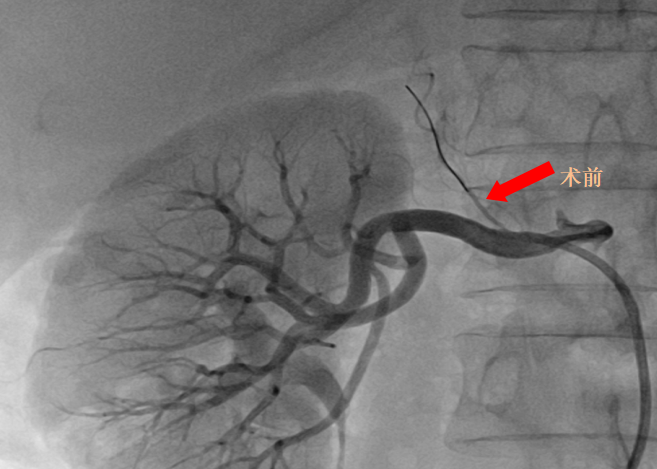

近期,黔南州中医医院心血管内科李莲主任团队詹玉柱副主任医师成功完成黔南首例经皮选择性肾上腺动脉栓塞术(SAAE)。手术顺利,患者恢复良好,标志着黔南州中医医院在继发性高血压的微创介入治疗领域取得重要突破,为区域该类患者提供了更精准、安全、微创的全新治疗。

黔南州中医医院心内科高血压亚专科团队为其进行了系统的继发性高血压筛查,肾上腺CT增强提示右侧肾上腺腺瘤(约12mm×7mm),伴左侧肾上腺增生,确诊为原发性醛固酮增多症所致高血压。

双侧肾上腺静脉取血提示右侧肾上腺为优势分泌侧。经与泌尿外科充分术前讨论,鉴于其右侧腺瘤体积较小,且合并左侧增生,外科手术切除腺瘤较困难,且患者拒绝外科手术治疗,故予右侧肾上腺动脉栓塞治疗。

(历时30分钟成功施行经皮选择性肾上腺动脉栓塞术)

术后第一天,患者仅服一种降压药,血压便控制理想,复查醛固酮、醛固酮/肾素比值均明显降低,血钾恢复至正常范围。术后第三天,患者康复出院。